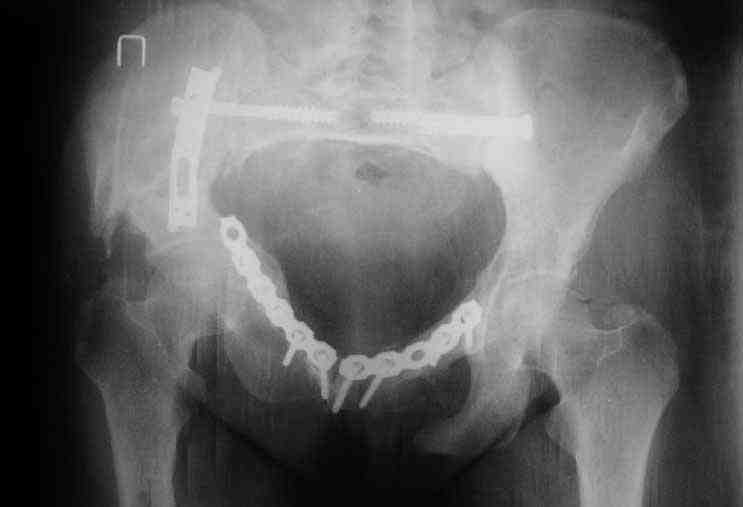

Картина на сегодня:

В настоящее время больная ходит без дополнительной опоры, боль в области таза не беспокоит, неудобств при сидении не испытывает, свободно проходит расстояние в 2-3км. Отмечается незначительная хромота, периодические боли в поясничной области низкой интенсивности, не требующие приема медикаментов, кроме того имеется вагинальный импинджемент. Срок после операции 1 год и 2 месяца.Было бы интересно услышать ваши комментарии. С уважением Агалаков М.В.